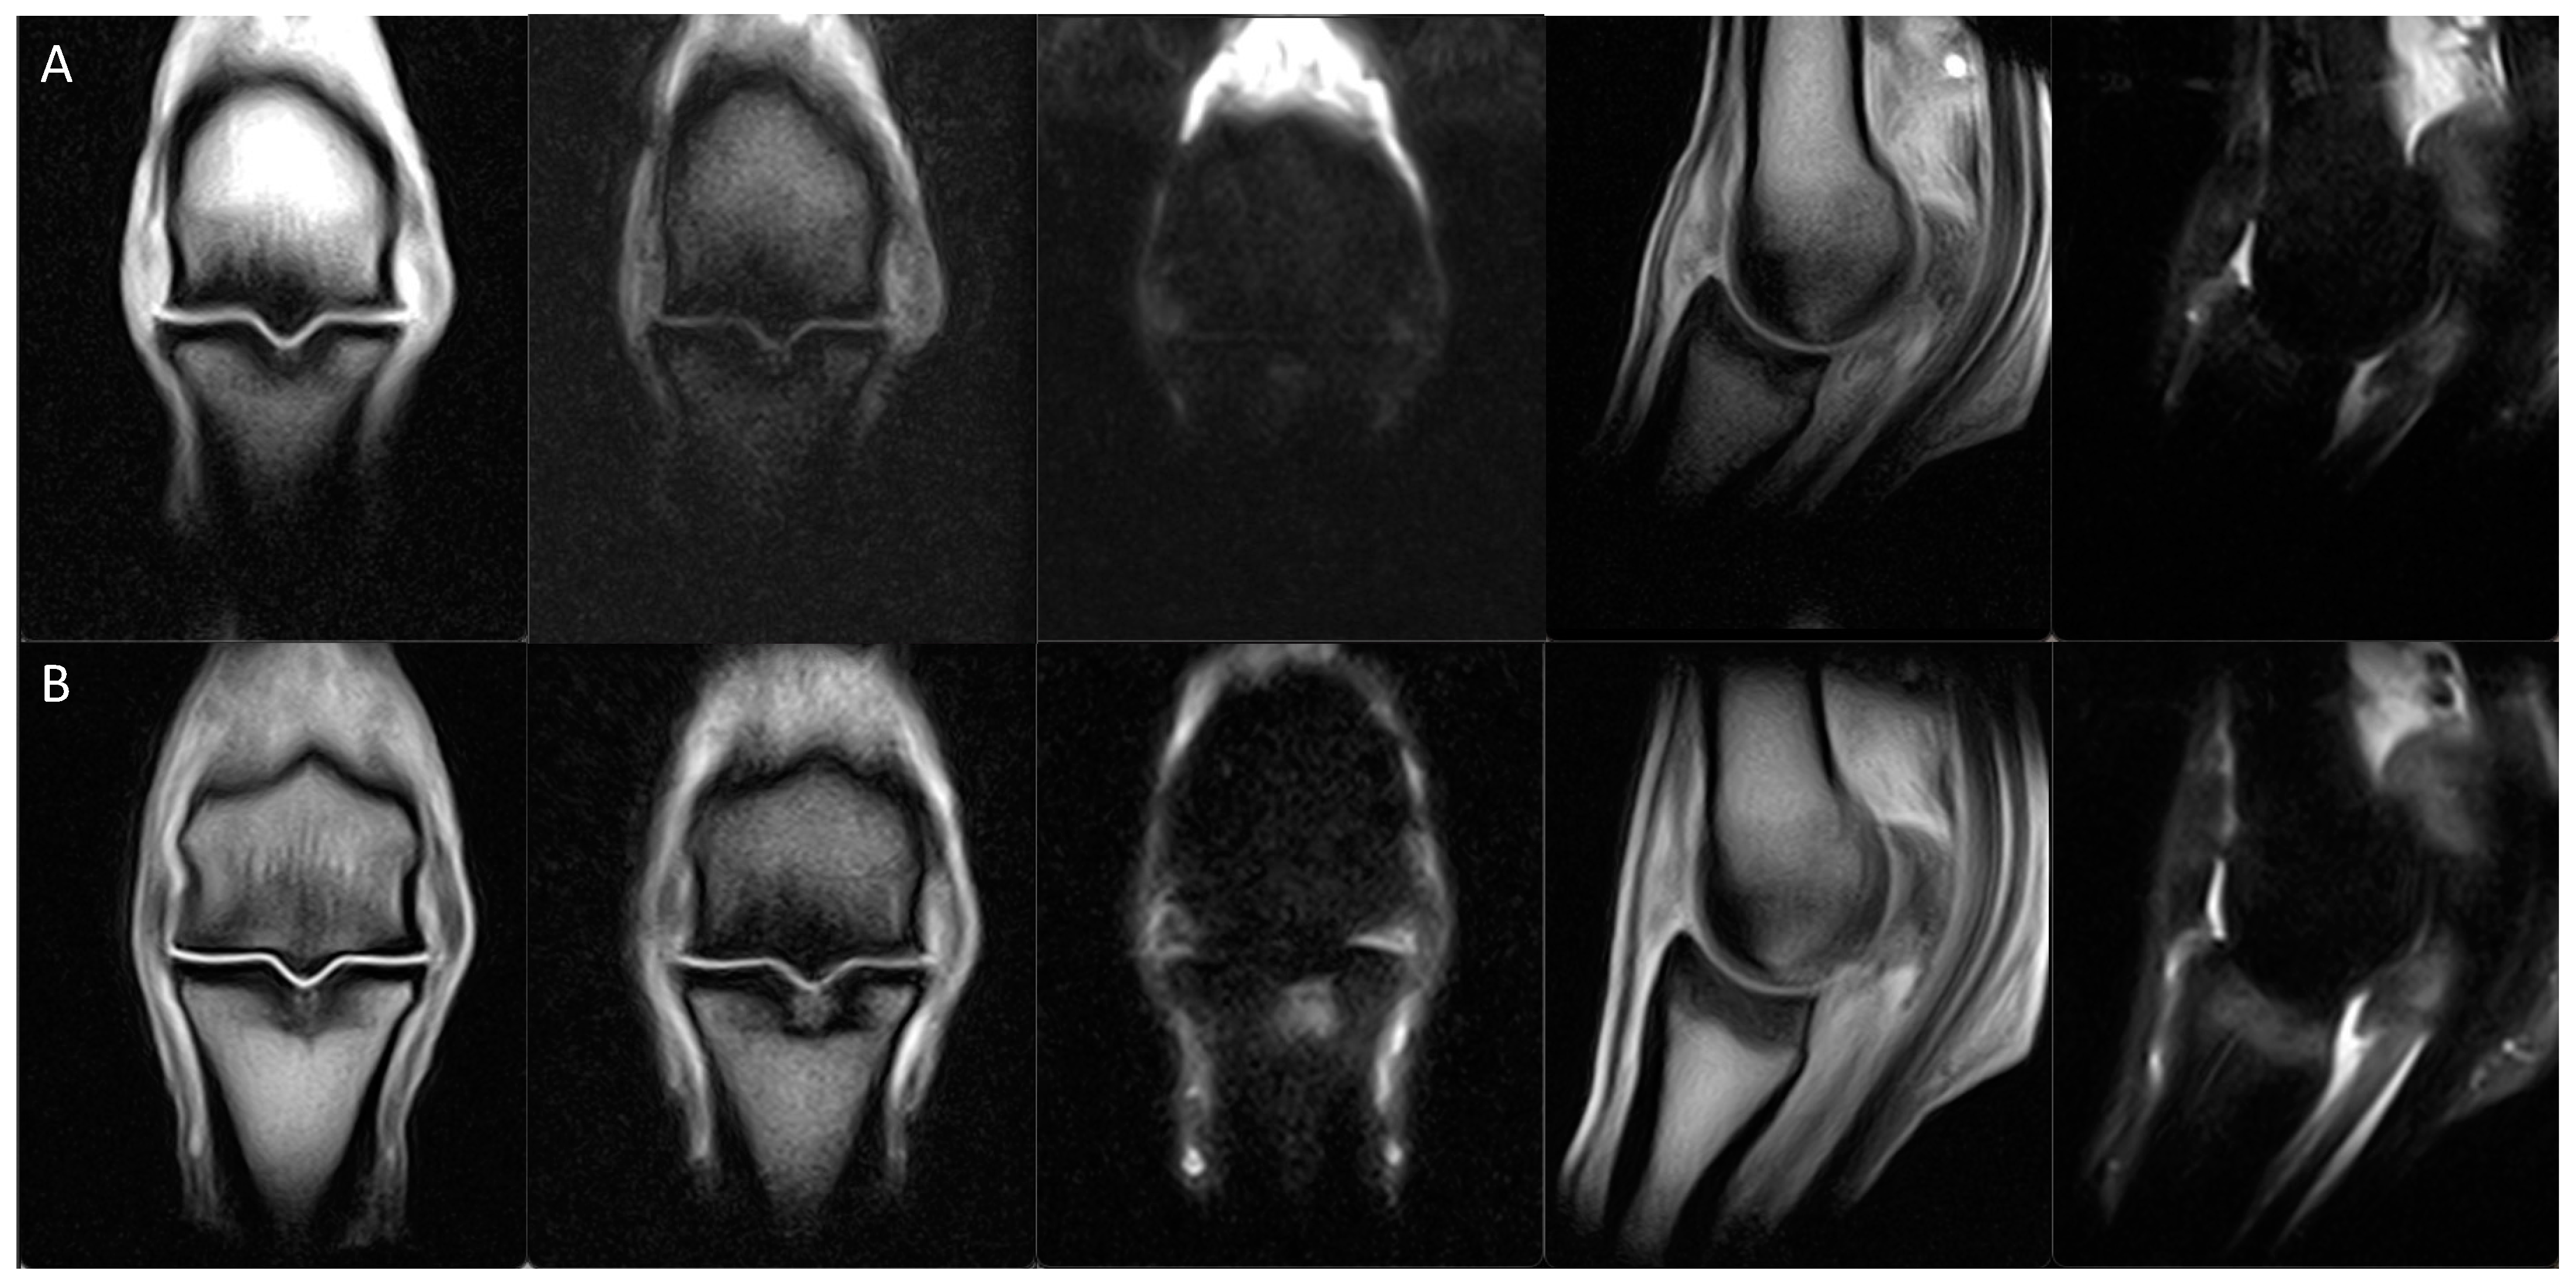

| SGD MRI Classification | Sub-Classifications and Description of Key Osseous Changes in the Sagittal Groove of the Proximal Phalanx | Absent Concurrent Features | Potential Concurrent Features | |

|---|---|---|---|---|

| 0 | Normal | No abnormalities | N/A | N/A |

| 1 | Small subchondral defect | (a) Minor, shallow defect in the chondro-osseous junction (typically ≤1 mm depth ± visible in only one slice) | Demineralisation, osseous densification, bone oedema-like signal | N/A |

| (b) Microfissure (proximodistally oriented, narrow, linear defect in the chondro-osseous junction that is contained within the subchondral bone plate, ≤3 mm length) | ||||

| 2 | Osseous densification | (a) Mild osseous densification of the subchondral ± trabecular bone, not extending to the proximal physis/physeal scar (proximodistal extent less than the equivalent depth of the SG) | Microfissure, demineralisation, bone oedema-like signal | Minor subchondral defect |

| (b) Moderate to severe osseous densification of the subchondral ± trabecular bone, extending to or beyond the proximal physis/physeal scar (proximodistal distance greater than one times the depth of the SG) | ||||

| 3 | Subchondral microfissure with osseous densification | (a) Subchondral microfissure (≤3 mm length) with mild osseous densification (does not reach the proximal physis/physeal scar) | Subchondral demineralisation or bone oedema-like signal | |

| (b) Subchondral microfissure (≤3 mm length) with moderate to severe osseous densification (extending to or beyond the proximal physis/physeal scar) | ||||

| 4 | Bone oedema-like signal within the subchondral ± trabecular bone | (a) Bone oedema-like signal within the subchondral ± trabecular bone | Microfissure, demineralisation | Minor subchondral defect, osseous densification of any extent |

| (b) Bone oedema-like signal within the subchondral ± trabecular bone with microfissure (short proximodistally oriented, narrow, linear defect contained within the subchondral bone plate (≤3 mm)) | Demineralisation | Osseous densification of any extent | ||

| (c) Bone oedema-like signal within the subchondral ± trabecular bone with subchondral demineralisation (unipartite or tripartite regions of demineralisation/resorption within the subchondral bone plate) | Microfissure, osseous densification of any extent | |||

| 5 | Incomplete macrofissure/fracture | Proximodistally oriented linear signal abnormality (>3 mm length; unipartite or tripartite configuration) extending through the subchondral bone and terminating within the trabecular bone | N/A | Demineralisation, osseous densification or bone oedema-like signal of any extent |

| 6 | Complete fracture | Proximodistally oriented linear signal abnormality extending through the subchondral and trabecular bone and exiting at the diaphyseal cortex or distal subchondral bone plate with the creation of two or more fragments | N/A | Demineralisation, osseous densification or bone oedema-like signal of any extent |